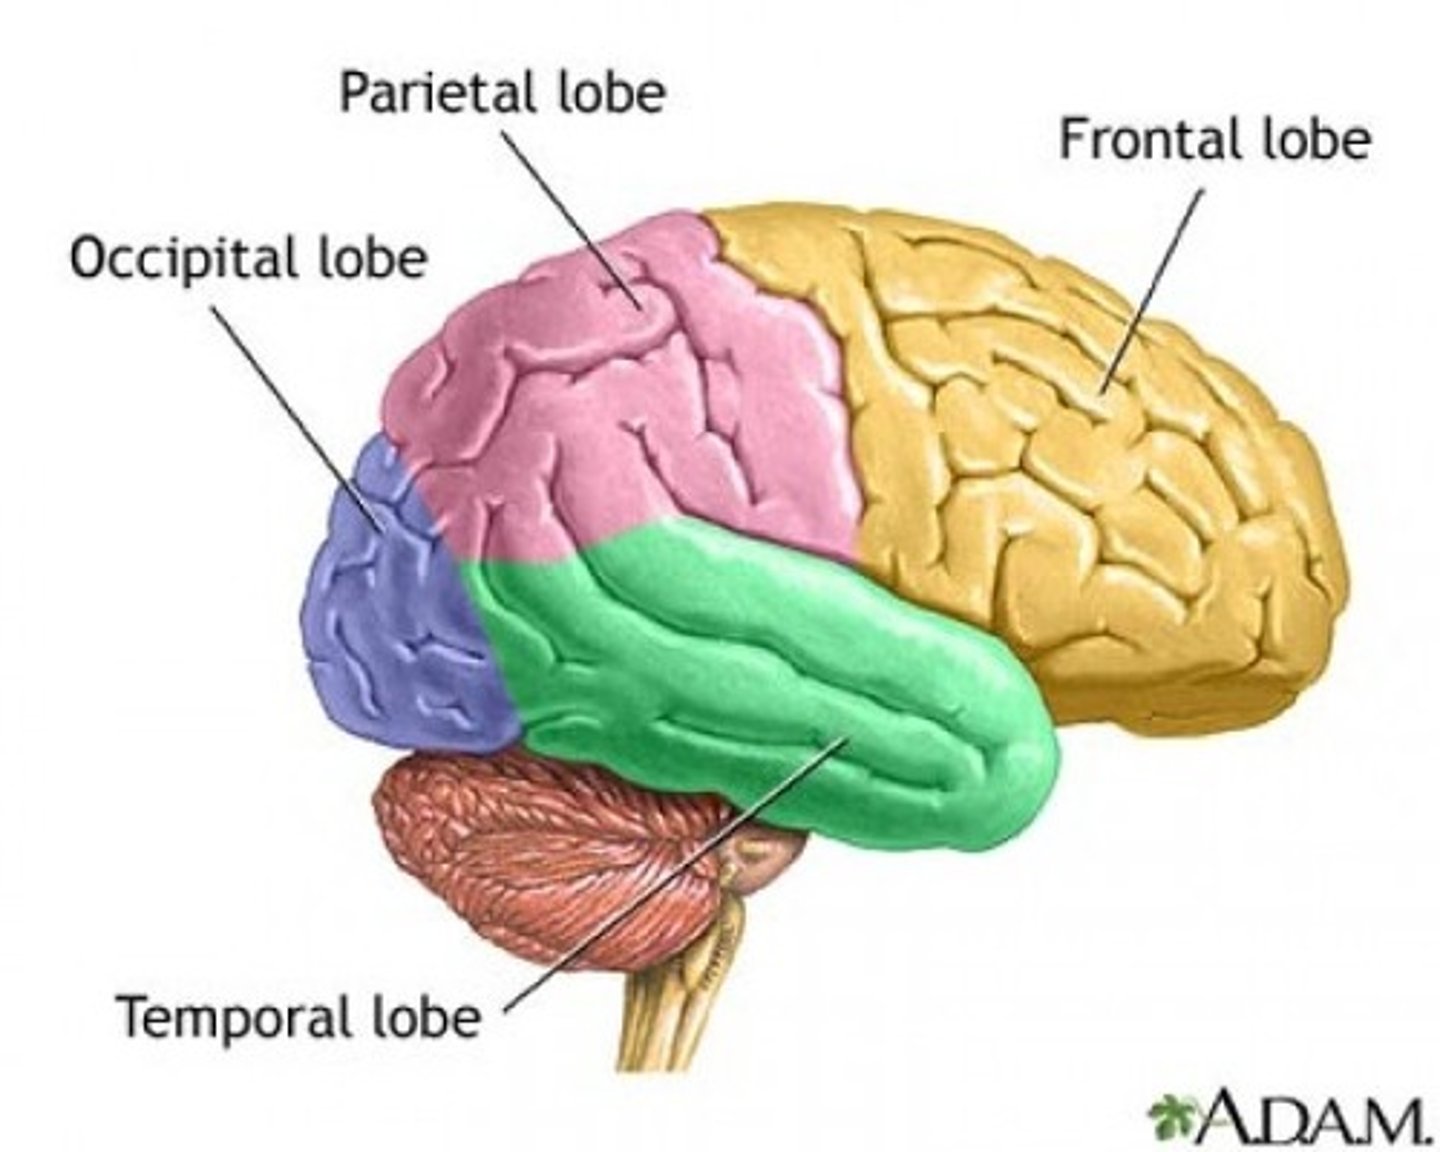

Lobes of the cerebrum

frontal, parietal, temporal, occipital

lateral cerebral sulcus

separates the frontal lobe from the temporal lobe

parieto-occipital sulcus

separates parietal and occipital lobes